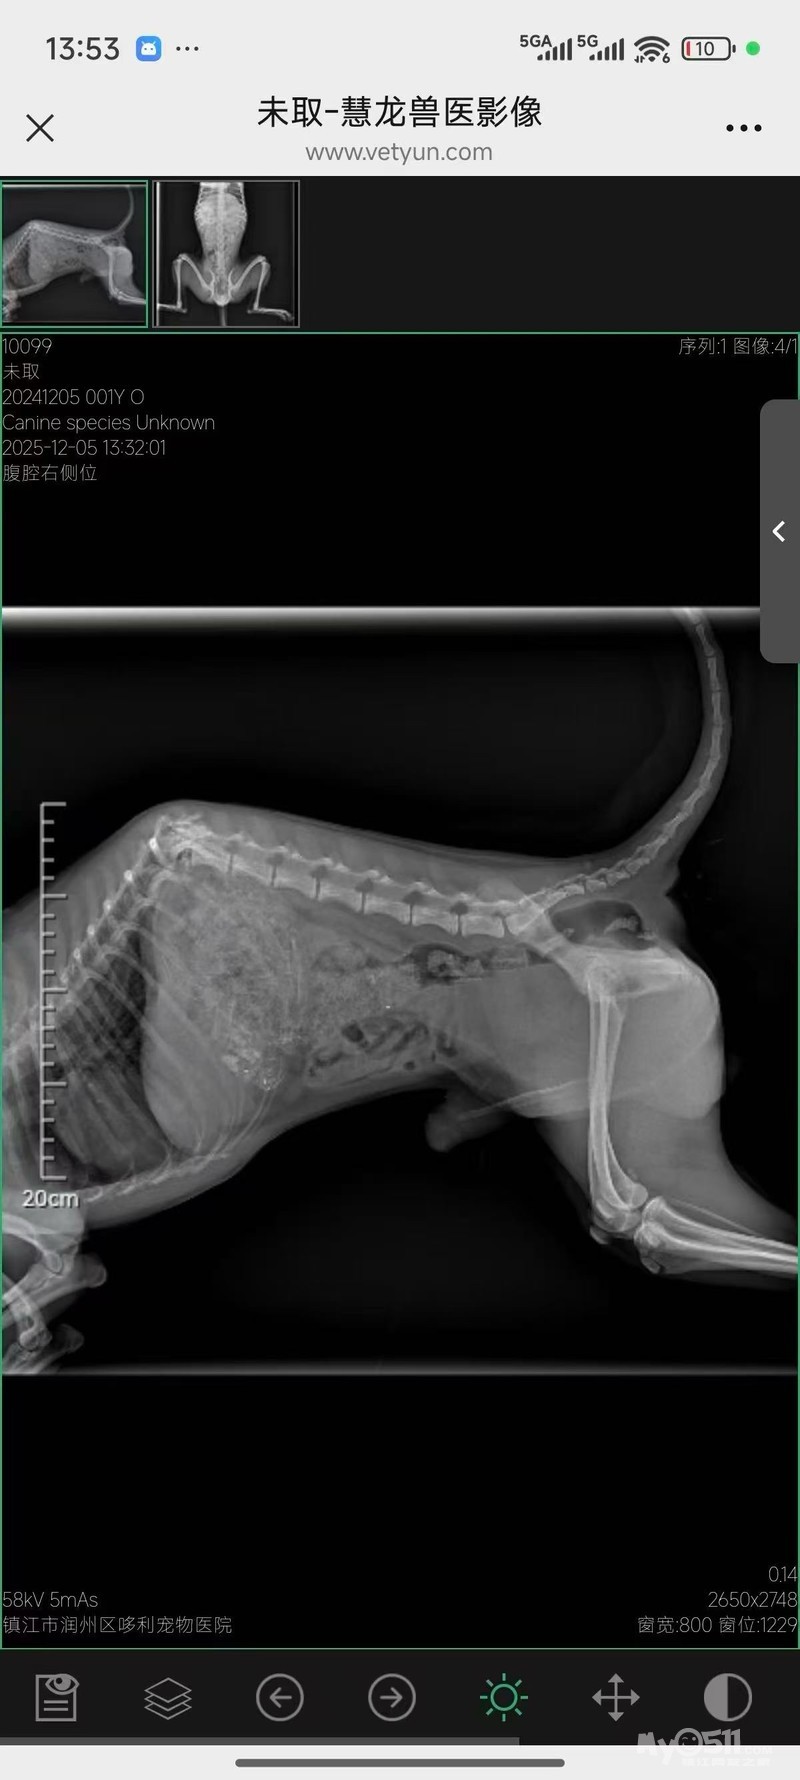

一个晚上过去,狗狗挺过来了,但是尿血,而且脊椎断裂,有深痛反应!目前医生已经用药治疗!